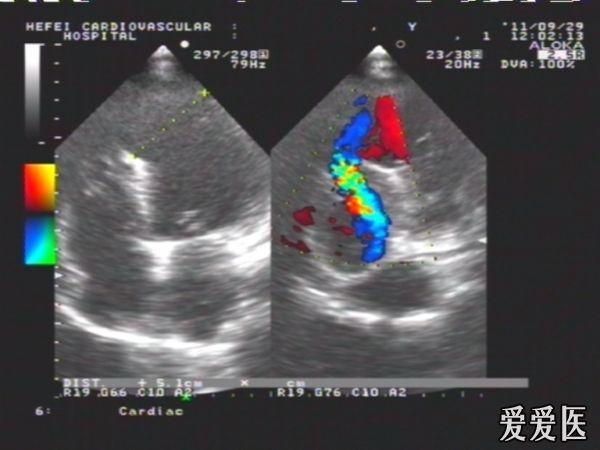

陈旧性前壁心梗继发肌部室间隔缺损典型病例

患者,女性,66岁,活动后心慌,胸闷2年,血压135/70mmHg,HR:78次/分。